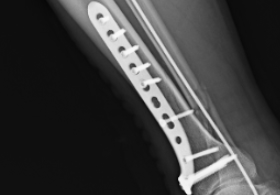

PART01危重患者緊急入院4月18日凌晨3時,一名因醉酒摔倒致頭部外傷、意識模糊的患者被緊急送至我院急診科。入院時患者頭部持續(xù)出血、右側(cè)肢體偏癱,頭顱CT檢查提示“左側(cè)額葉腦挫裂傷合并左側(cè)額顳部硬膜下血腫”,病情危重。凌晨3點急診CT神經(jīng)外科團隊迅速響應,嚴密監(jiān)測患者生命體征。然而,隨著時間推移,患者頭痛加劇,復查CT顯示顱內(nèi)血腫范圍擴大,腦組織受壓明顯,需立即手術(shù)干預。上午9點CT復查PART02血腫擴大危及生命面對緊急情況,神經(jīng)外科趙堅柱副主任醫(yī)師帶領(lǐng)團隊快速制定手術(shù)方2025-04-26